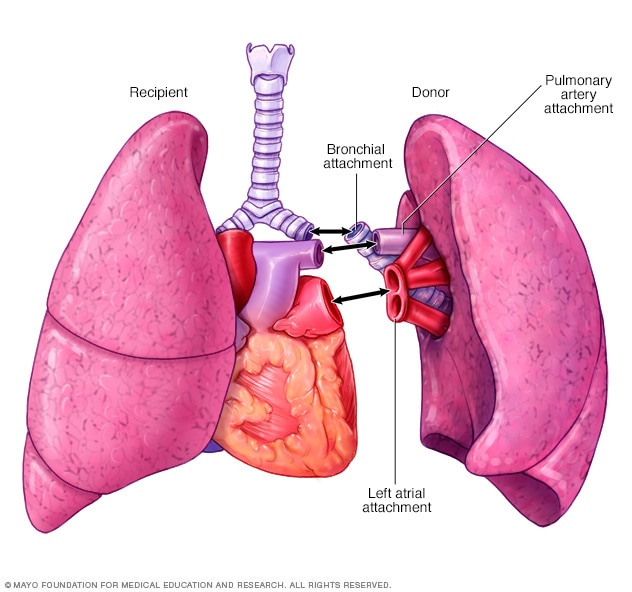

Durante un trasplante de pulmón, los cirujanos extirpan el pulmón enfermo y luego conectan el pulmón del donante a las vías respiratorias y a los vasos sanguíneos que se unen con el corazón.

Según la afección médica del paciente, el trasplante consistirá en reemplazar uno de los pulmones o ambos. En determinadas situaciones, los pulmones pueden trasplantarse junto con el corazón de un donante.

El cirujano hará un corte en el pecho para extraer el pulmón dañado. Las vías respiratorias principales conectadas a ese pulmón y los vasos sanguíneos que se encuentran entre ese pulmón y el corazón se conectarán al pulmón donado. En algunos trasplantes de pulmón, es posible que se te conecte a una bomba de circulación extracorpórea, que hace circular la sangre durante el procedimiento.